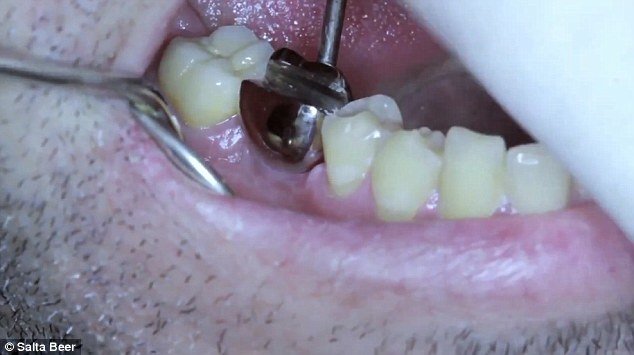

A marca de cerveja argentina Salta, em parceria com a agência Ogilvy & Mather Argentina, criou uma forma de implante dentário que promete ser a solução para quando você estiver sem um abridor de garrafas.

A campanha é voltada a jogadores de rugby, uma vez que o esporte por vezes acaba provocando a quebra de alguns ossos ou dentes perdidos.

Embora reforce estereótipos envolvendo a modalidade, e apesar dos diretores da agência Ogvily & Mather, Maximiliano Maddalena e Javier Mentasti, ficarem temorosos acerca da campanha, a ideia provou ser um sucesso, com muitas pessoas, incluindo atletas argentinos, aceitando fazer o implante.

Contudo, embora a ideia pareça ser útil, especialmente para quem sempre pensou abrir uma garrafa com a boca, o implante pode ser perigoso.

De acordo com o Dr. Bruno Puglise, que deu entrevista a um portal de notícias, abrir objetos desta forma pode causar fraturas na coroa do dente e raiz, afetar restaurações e próteses e até mesmo sobrecarregar articulações.